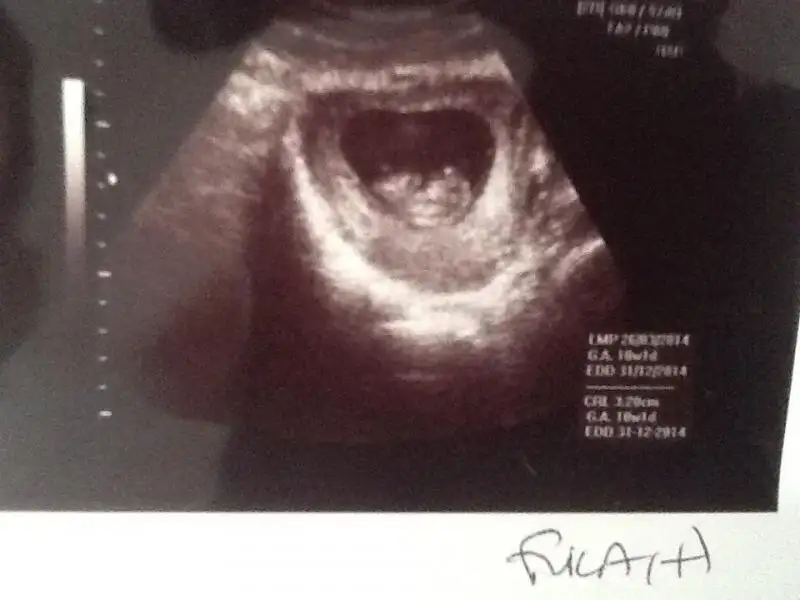

Bu ucuncu oldugu icin artik deneyimliyim tabi hemen anladim ve bir test aldim cikacagindan cok emindim esim bile yok canim demisti gorunce o da sasirdi :) dr a gittigimde daha kese bile yoktu kan tahlilinden ogrendik bugun itibari ile tam 11+2 yiz allah isteyen herkese versin insallah